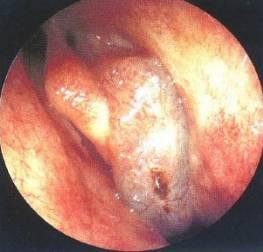

1、内镜检查:来源于中鼻道、嗅裂的黏脓性分泌物,中鼻道粘膜充血、水肿或有鼻息肉。

• 鼻腔检查:前鼻镜、鼻内窥镜。

图2 治疗后